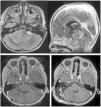

Lateral-type posterior fossa ependymomas are a well-defined subtype of tumours both clinically and pathologically, with a poor prognosis. Their incidence is low and surgical management is challenging. The objective of the present work is to review our series of lateral-tye posterior fossa ependymomas and compare our results with those of previous series.

ResultsMean age of our patients was 3.75 years. 6 cases presented with hydrocephalus. Mean tumour volume at diagnosis was 61 cc. A complete resection was achieved in six cases and a near-total resection in one patient. 5 patients transiently required a gastrostomy and a tracheostomy. Mean follow-up was 58 months. One case progressed along this period and eventually died. 4 cases of hydrocephalus required a ventriculoperitoneal CSF shunt and two were managed with a third ventriculostomy. At last follow-up 4 patients carried a normal life and two displayed a mild restriction according to Lansky´s scale.